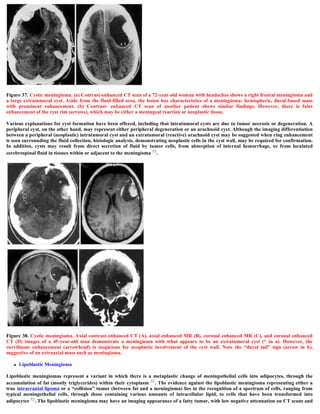

Figure 39. Lipoblastic meningioma. (A) Contrast-enhanced CT scan of a 60-year-old white woman with a 2-week history of seeing flashing

lights and difficulty in reading shows a well-circumscribed low-attenuation lesion. The rim of the lesion is enhanced, and faint intratumoral

strands of enhancing tissue are seen. Sagittal TI-weighted (B) and axial T2-weighted (C) MR images demonstrate a signal intensity within the

lesion that is similar to that of subcutaneous fat. (D) Gross specimen shows a well-circumscribed mass and the yellowish color of fatty

metaplasia.

Figure 40. Lipoblastic meningioma. (A) Contrast-enhanced CT scan of a 36-year-old white woman with progressive gait difficulty

demonstrates a left frontoparietal mass with an extremely low-attenuation (compatible with fat) center and a thick enhancing rind. Note the

small mound of hyperostosis (*) underlying the central enhancing nodule of meningioma (arrow). (B) Right external carotid arteriogram

shows enlargement of the middle meningeal artery that supplies the tumor. The spoke-wheel pattern of the fine radial arterioles is

characteristic of meningioma. The ‘ ‘dimple’ ‘ in the center of the neovascularity (arrow) corresponds to the mound of bone seen in a. (C)

Photograph of the cut specimen shows the attachment of the tumor to the dura mater (arrows) and the yellow-white color typical of

lipoblastic meningioma.

 Lipoblastic Meningioma

Lipoblastic meningiomas represent a variant in which there is a metaplastic change of meningothelial cells into adipocytes, through the

accumulation of fat (mostly triglycerides) within their cytoplasm 52. The evidence against the lipoblastic meningioma representing either a

true intracranial lipoma or a “collision” tumor (between fat and a meningioma) lies in the recognition of a spectrum of cells, ranging from

typical meningothelial cells, through those containing various amounts of intracellular lipid, to cells that have been transformed into

adipocytes 52. The lipoblastic meningioma may have an imaging appearance of a fatty tumor, with low negative attenuation on CT scans and

a short TI relaxation time with high signal intensity on T1-weighted MR images 53,54. Xanthomatous change in meningioma can be

differentiated histologically from the lipoblastic variant; however, since both contain excess lipid, the nadiologic distinction may be difficult.

However, the lipoblastic meningioma may be suggested when the fatty regions are larger, are more confluent, and do not have prominent

enhancement 53.